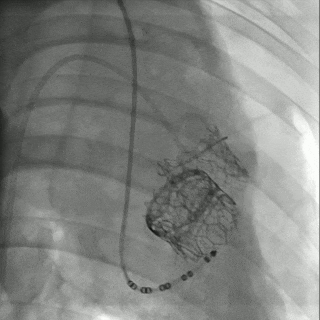

多枚二尖瓣瓣中瓣及TAVR球扩瓣完成植入后造影

佰仁微创学院旨在助力年轻一代医师精进技术水平。本次实战训练营中,所有学员均得到了大动物活体实战演练的机会,在带教专家的悉心指导下,成功完成经导管主动脉瓣及经导管瓣中瓣的植入的实战训练。其中每头大动物二尖瓣位植入3枚瓣中瓣,模拟了生物瓣植入后40-50年的全生命周期管理过程。TEE测量结果显示:25号限位可扩张瓣膜在6 atm压力球囊扩张后,瓣架充分展开,直径扩大2mm,内部植入27号瓣中瓣后,压差甚至较植入瓣中瓣前更低。得益于初次选择的佰迈思限位可扩张生物瓣的瓣环可扩张的独特优势,植入第三枚瓣中瓣后仍然保持了出色的血流表现,二尖瓣平均跨瓣压差仍能保持在5mmHg以内。主动脉瓣位植入Renatus®经导管主动脉瓣,植入过程中得益于可调弯输送器的辅助,过弓顺滑,释放时保证了更好的同轴性。